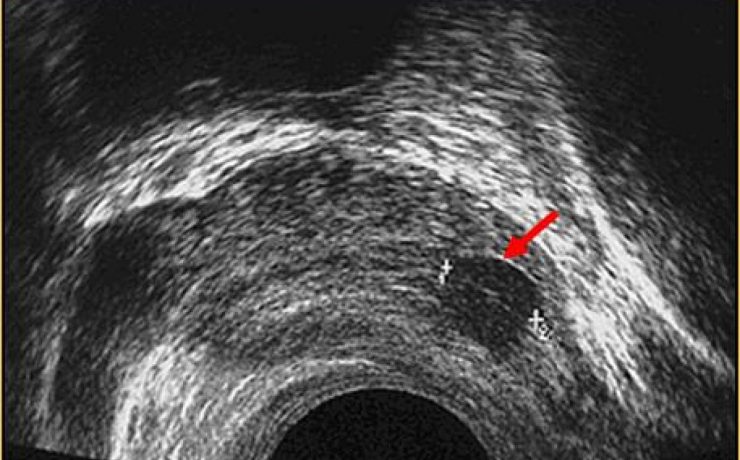

Revista Anales de Radiología de México. Ultrasonido Tiroideo en pacientes dediatricos del HIM, con diagnostico clínico de Tiroiditis de Hashimoto. México 2012 (11) – 1. Se revisaron 64 pacientes, por US más frecuente en mueres 9/1, y la lesión común es nódulo único, hipoecogénico, con contenido sólido, con vascularidad periférica.